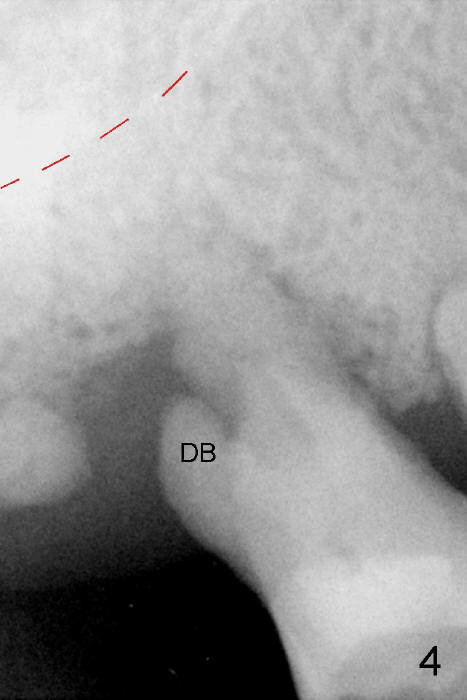

One year later, a 68-year-old lady requests treatment for the same tooth with almost identical conditions (Fig.4-6). Immediate implant is placed with immediate outcome. The difference between these cases is experience and practice.